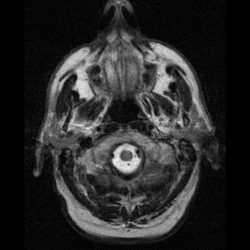

تصوير للرأس بالرنين المغناطيسي | |

التصوير العصبي

يستخدم التصوير المغناطيسي للكشف عن السرطانات العصبية لأنها أكثر حساسية من بقية الأساليب التصويرية الأخرى مثل الرسم السطحي بواسطة الحاسوب [1] خاصة عند البحث عن الأورام الصغيرة. التباين اللوني الذي يمكن لهذا الأسلوب انتاجه بين المادة الرمادية والمادة البيضاء يجعله الخيار الأفضل في كثير من الحالات.[2] بما أن آلات التصوير المغناطيسي بإمكانها التقاط العديد من الصور خلال فترة زمنية قصيرة، فهي تساعد العلماء على فهم كيف يستجيب الدماغ للتحفيزات العصبية المختلفة مما يساعدهم على تشخيص المرض. الرنين المغناطيسي يساعد على تشخيص العديد من الأمراض مثل الجنون، الأمراض الدماغية والوعائية و الصرع.